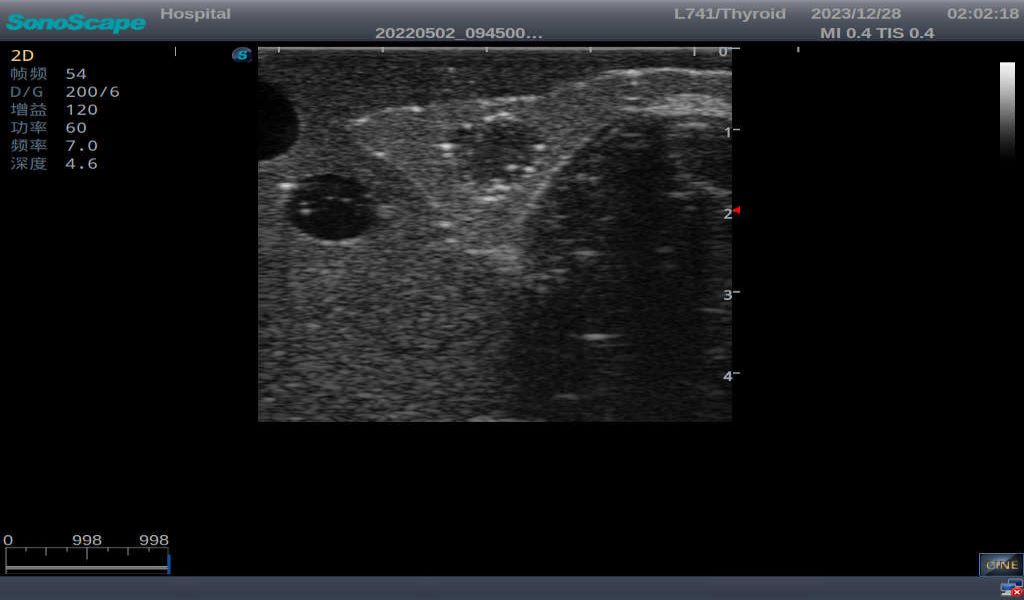

3)       It comes with four (4) thyroid modules and can show five (5) ultrasonic images: normal thyroid, thyroid adenoma, thyroid cancer, nodular goiter, thyroid cyst

Nodular goiter with irregular border and varying sizes of low echo, isoechoic, or high echo nodules

Thyroid cyst, which fluid area, dark and echo-free area can be seen